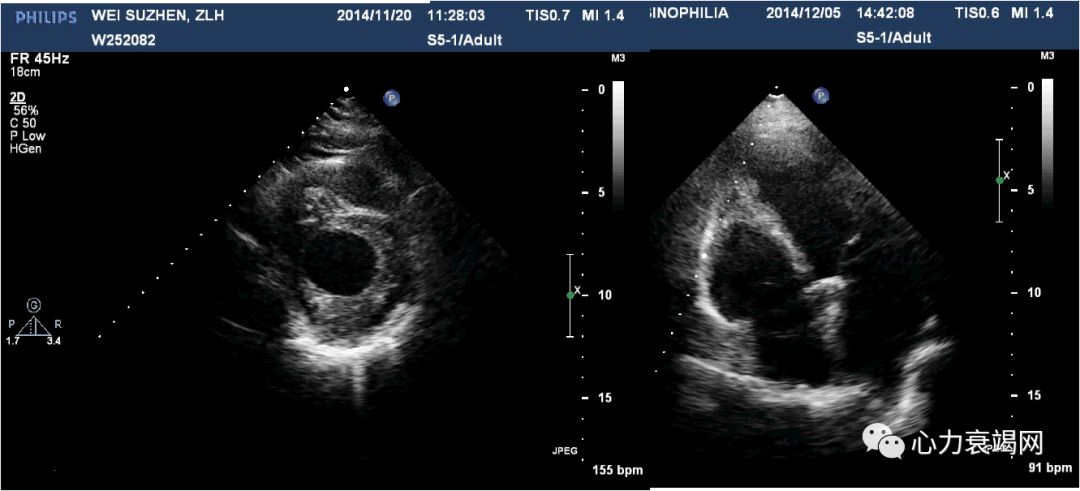

治疗前

2个月后

激素及抗心衰治疗后